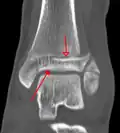

CT

Les tomodensitogrammes peuvent être indiqués en cas de risque de fracture fragmentée ou de fracture impliquant la surface articulaire[9]. Cette imagerie peut être utilisée pour la planification chirurgicale.